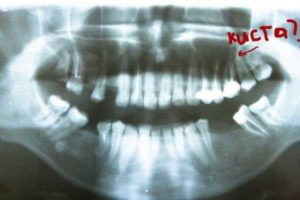

Главный способ диагностики – рентген, так как он показывает пораженные участки как затемненные.

диагностическая методика, используемся для определения кисты – рентген. На КТ и МРТ врач направляет пациента в случае необходимости.

- рентген;